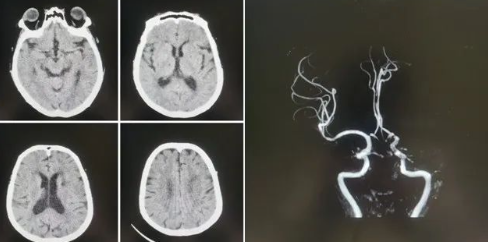

77歲的張阿姨(化名)家住公主嶺市劉房子街道,在活動中突發(fā)意識不清、言語不能,家屬在發(fā)病后1小時內(nèi)緊急將患者送至我院急診。急診科醫(yī)生第一時間查看病人,患者高齡,進展性意識不清、言語不能,雙眼向左側(cè)凝視,壓眶疼痛刺激下左側(cè)肢體可抬起,右側(cè)肢體肌力0級,緊急啟動卒中救治綠色通道,立即進行頭CT檢查,排除出血后,考慮急性缺血性腦卒中,因患者發(fā)病時間短,緊急聯(lián)系卒中中心團隊,國文醫(yī)院卒中中心丁金明主任第一時間聯(lián)系影像科進行了頭部核磁血管檢查,確診為左側(cè)大腦中動脈急性閉塞。

緊急啟動導(dǎo)管室、麻醉科,在導(dǎo)管室、麻醉科人員的配合下在全麻下進行了腦血管造影術(shù),造影顯示:III型弓,左側(cè)大腦中動脈M1段閉塞,余血管未見異常,立即進行左側(cè)大腦中動脈閉塞取栓術(shù),因為患者III型弓,動脈硬化重,血管迂曲嚴重,在泥鰍導(dǎo)絲指引下,利用同軸技術(shù)(6F長鞘+5F多功能造影管)反復(fù)嘗試超選左側(cè)頸總動脈失敗。

在神經(jīng)介入團隊丁金明主任、朱洪波副主任共同努力下,通過交換技術(shù)成功超遠目標(biāo)血管,釋放取栓支架,通過取栓支架取出一團塊狀血栓,成功開通左側(cè)大腦中動脈血流,挽救了患者的生命,術(shù)后頭CT檢查未見出血,轉(zhuǎn)入重癥監(jiān)護病房進一步治療。

神經(jīng)介入團隊丁金明主任表示:機械取栓術(shù)是急性腦梗死治療的終極武器,但需要嚴格把握時間窗與適應(yīng)癥。此例手術(shù)的成功得益于三大要素:1、患者及時送醫(yī)及我院卒中救治綠色通道的高效性。2、多學(xué)科高效協(xié)作:神經(jīng)介入科聯(lián)合急診科、影像科、麻醉科等多團隊無縫銜接,實現(xiàn)診斷-決策-手術(shù)一體化救治。3、團隊對手術(shù)細節(jié)的精準(zhǔn)把控和術(shù)中高清影像導(dǎo)航,成功清除顱內(nèi)大血管血栓,術(shù)后血流恢復(fù)達‘TICI 3級’(完全再通),未來我們將進一步優(yōu)化救治流程,讓更多卒中患者重獲新生。